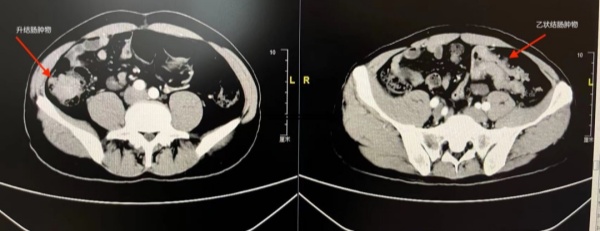

3.CT或MRI检查

像给肚子拍“全景照片”,除了看看肠壁是否有不规则肿块以及病灶的具体位置,还可以发现癌细胞是否扩散到肝、肺等器官。